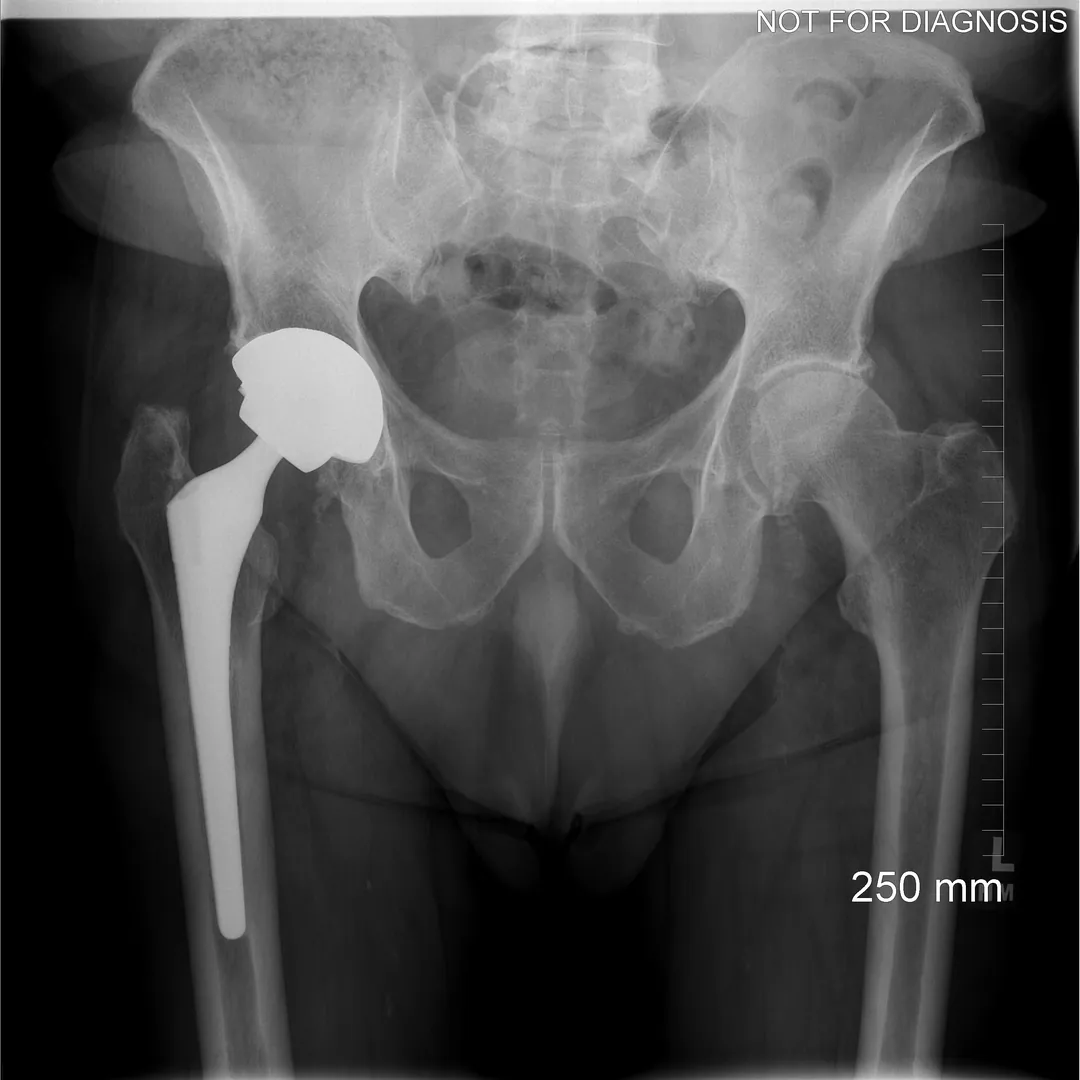

Revision Total Hip Replacement (Revision THA)

What Is a Revision Total Hip Replacement?

A revision total hip replacement (revision THA) is a surgical procedure performed to replace or repair a previous hip replacement that is no longer functioning well.

Unlike a primary (first-time) hip replacement, revision surgery is more complex and tailored to the specific problem affecting the existing implant.

• May require removal of one or more existing components

• May involve bone grafts, specialized implants, or reconstruction techniques

Clinical View